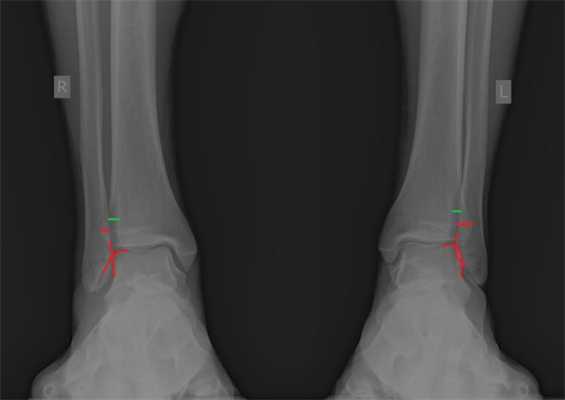

При детальном изучении снимков определяется увеличение межберцовой щели до 7,5 мм, уменьшения зоны перекрытия большеберцовой и малоберцовой костей до 5 мм, отсутствие на стороне поражения перекрытия тени таранной кости и малоберцовой кости.

На рентгенограмме костей правого и левого голеностопных суставов в прямой проекциии, снимки стоя - справа определяются признаки повреждения дистального межберцового синдесмоза - степень взаимного перекрытия берцовых костей 5мм (в норме больше 6мм) увеличенное большеберцовое - малоберцовое пространство - 7.5мм (в норме до 6мм).

При выполнении стресс рентгенограмм определяется выраженная латеральная нестабильность голеностопного сустава.